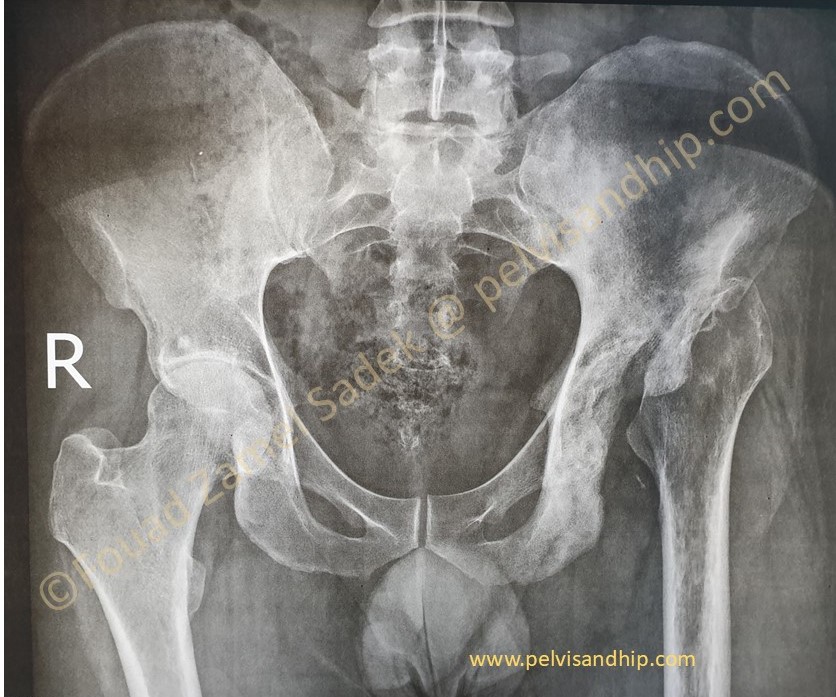

Case 2: dysplastic hip causing secondary ostearthritis with more significant acetabular deficiency (please click on the picture)